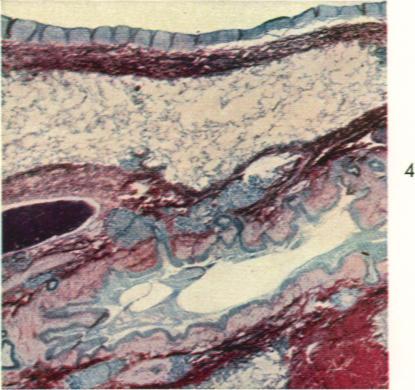

Human inhalation anthrax. A report of three fatal cases.

Am J Pathol. 1960 Apr;36(4):457-71.